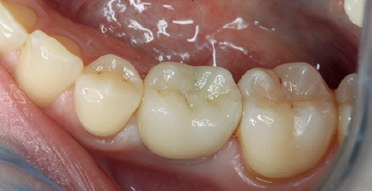

Dabei nutzte ich das durch die provisorische Versorgung bereits bestehende Emergenzprofil des Weichgewebes für eine optimale definitive Versorgung. Etwaige okklusale Differenzen während der Einheildauer ließen sich auf diese Weise gut ausgleichen. Die finale Versorgung habe ich 2-teilig ausgeführt. Die Unterkonstruktion wurde mittels eines individuellen Zirkonabutments aus inCoris Meso Block gefräst und anschließend gesintert (CEREC SpeedFire). Die Krone wurde aus einem Celtra Duo LT Block geschliffen und im Anschluss individuell bemalt und glasiert (Abb. 18 bis 22).